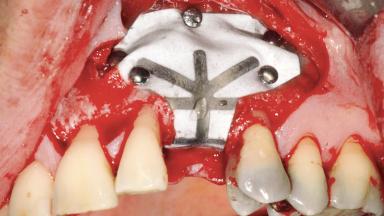

Guided Bone Regeneration (GBR) with a Particulated Autologous Graft and a ePTFE-Reinforced Membrane for Vertical Augmentation of a Single-Tooth Edentulous Space in the Esthetic Zone

A 47-year-old Caucasian woman with a single-tooth edentulous space at the site of the left maxillary canine was referred for treatment. She had undergone traumatic extraction of this impacted canine several months before referral. Her chief complaint was the dissatisfying appearance of her smile. The patient desired a stable and esthetic rehabilitation of the site. Her dental history showed no evidence of periodontal disease or bruxism. She had no systemic diseases, was not taking any medications, and did not smoke. The extraoral examination revealed a high lip line and an inadequate soft-tissue volume at the defective canine site. Large black triangles were visible between the canine and its adjacent teeth.